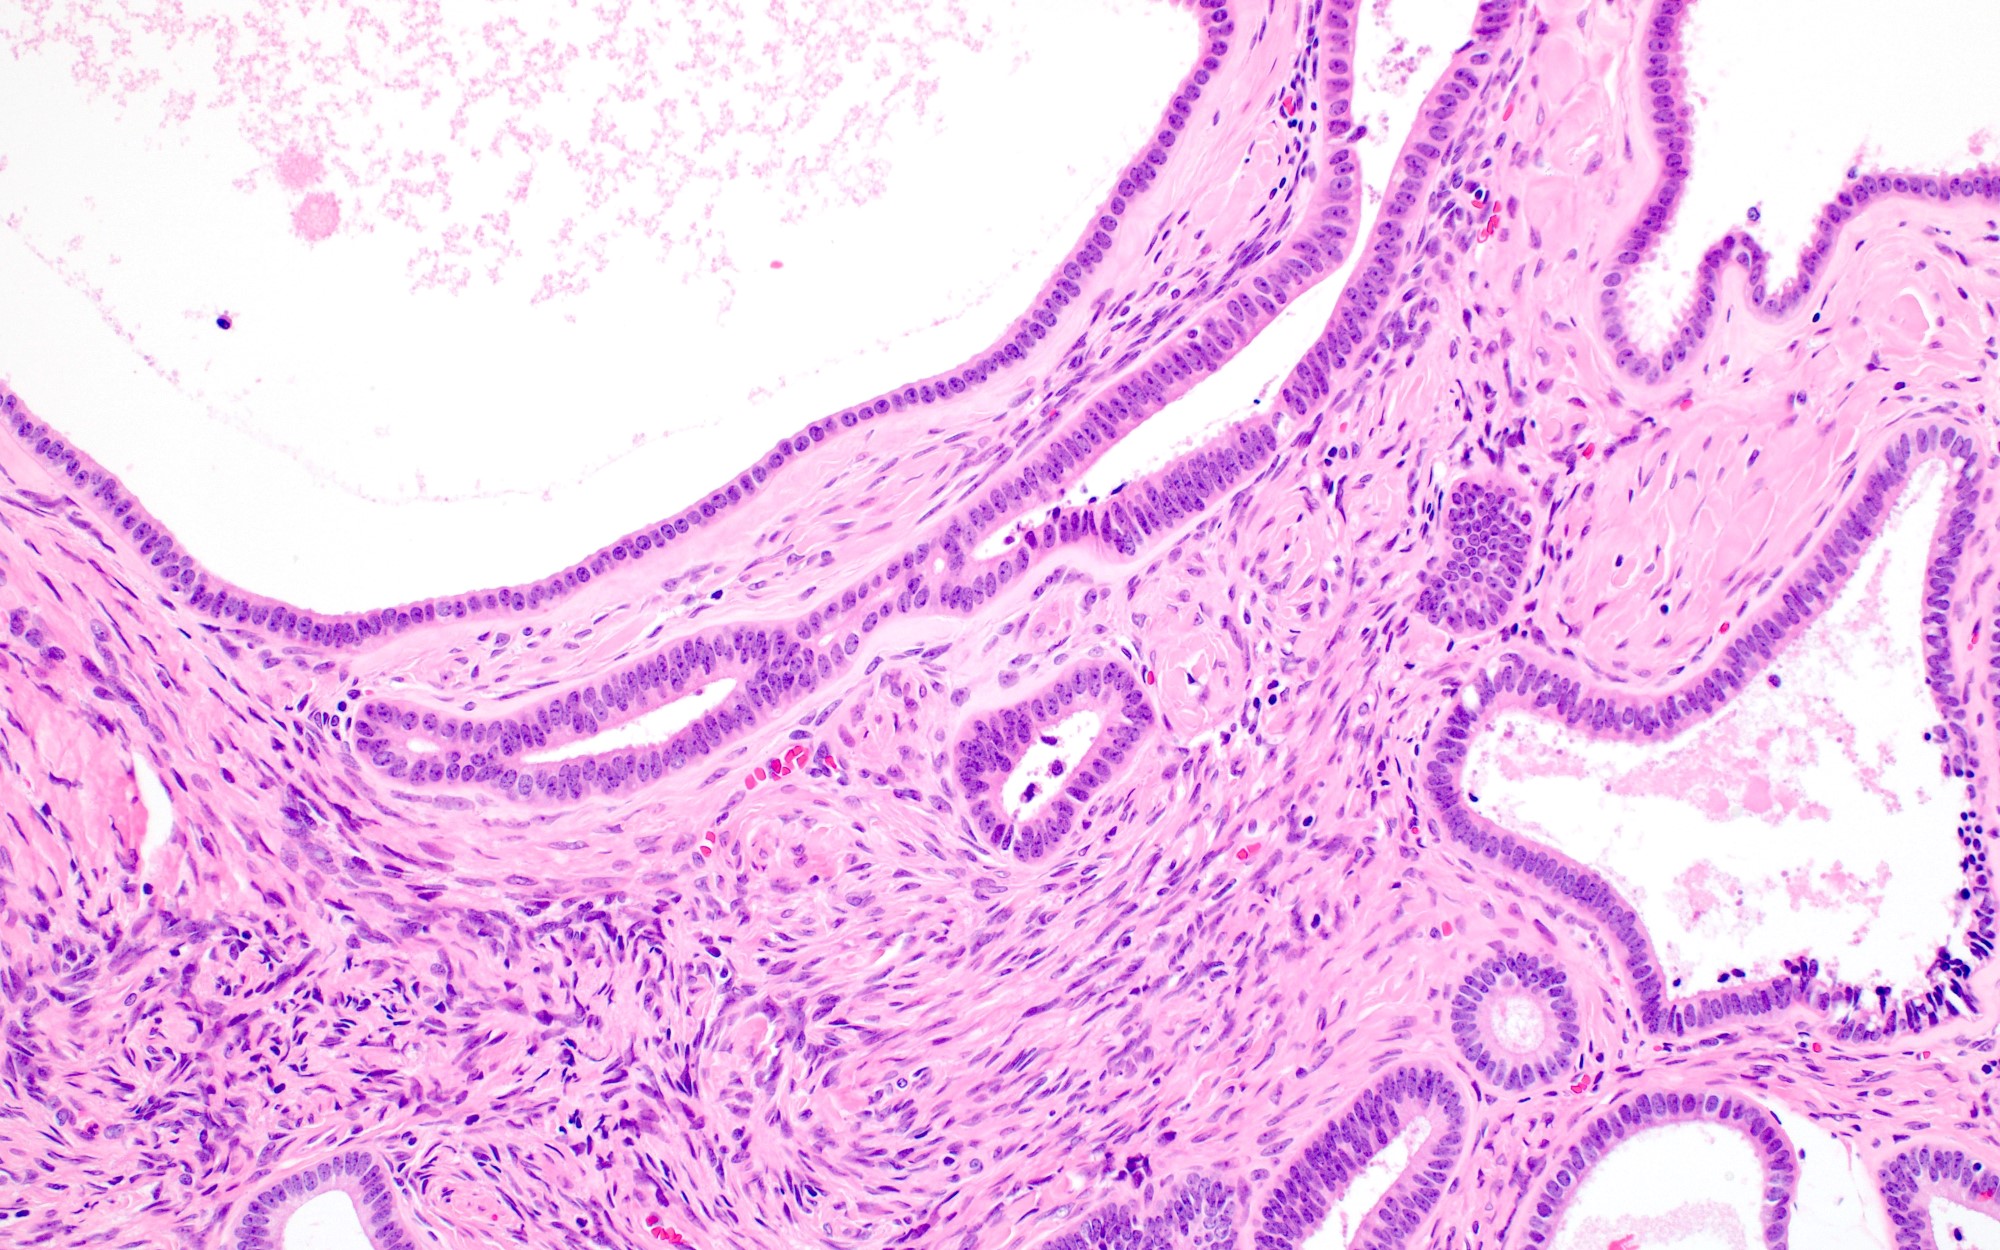

Microscopic (histologic) description

- Cystadenoma:

- Cyst lined by benign endometrioid epithelium without endometrial stroma

- Endometriosis may be present

- Adenofibroma:

- Widely spaced benign endometrioid glands associated with fibromatous stroma

- Endometriosis may be present

- Areas of mucinous or serous differentiation can be seen (Histopathology 2021;78:445)

Microscopic (histologic) images